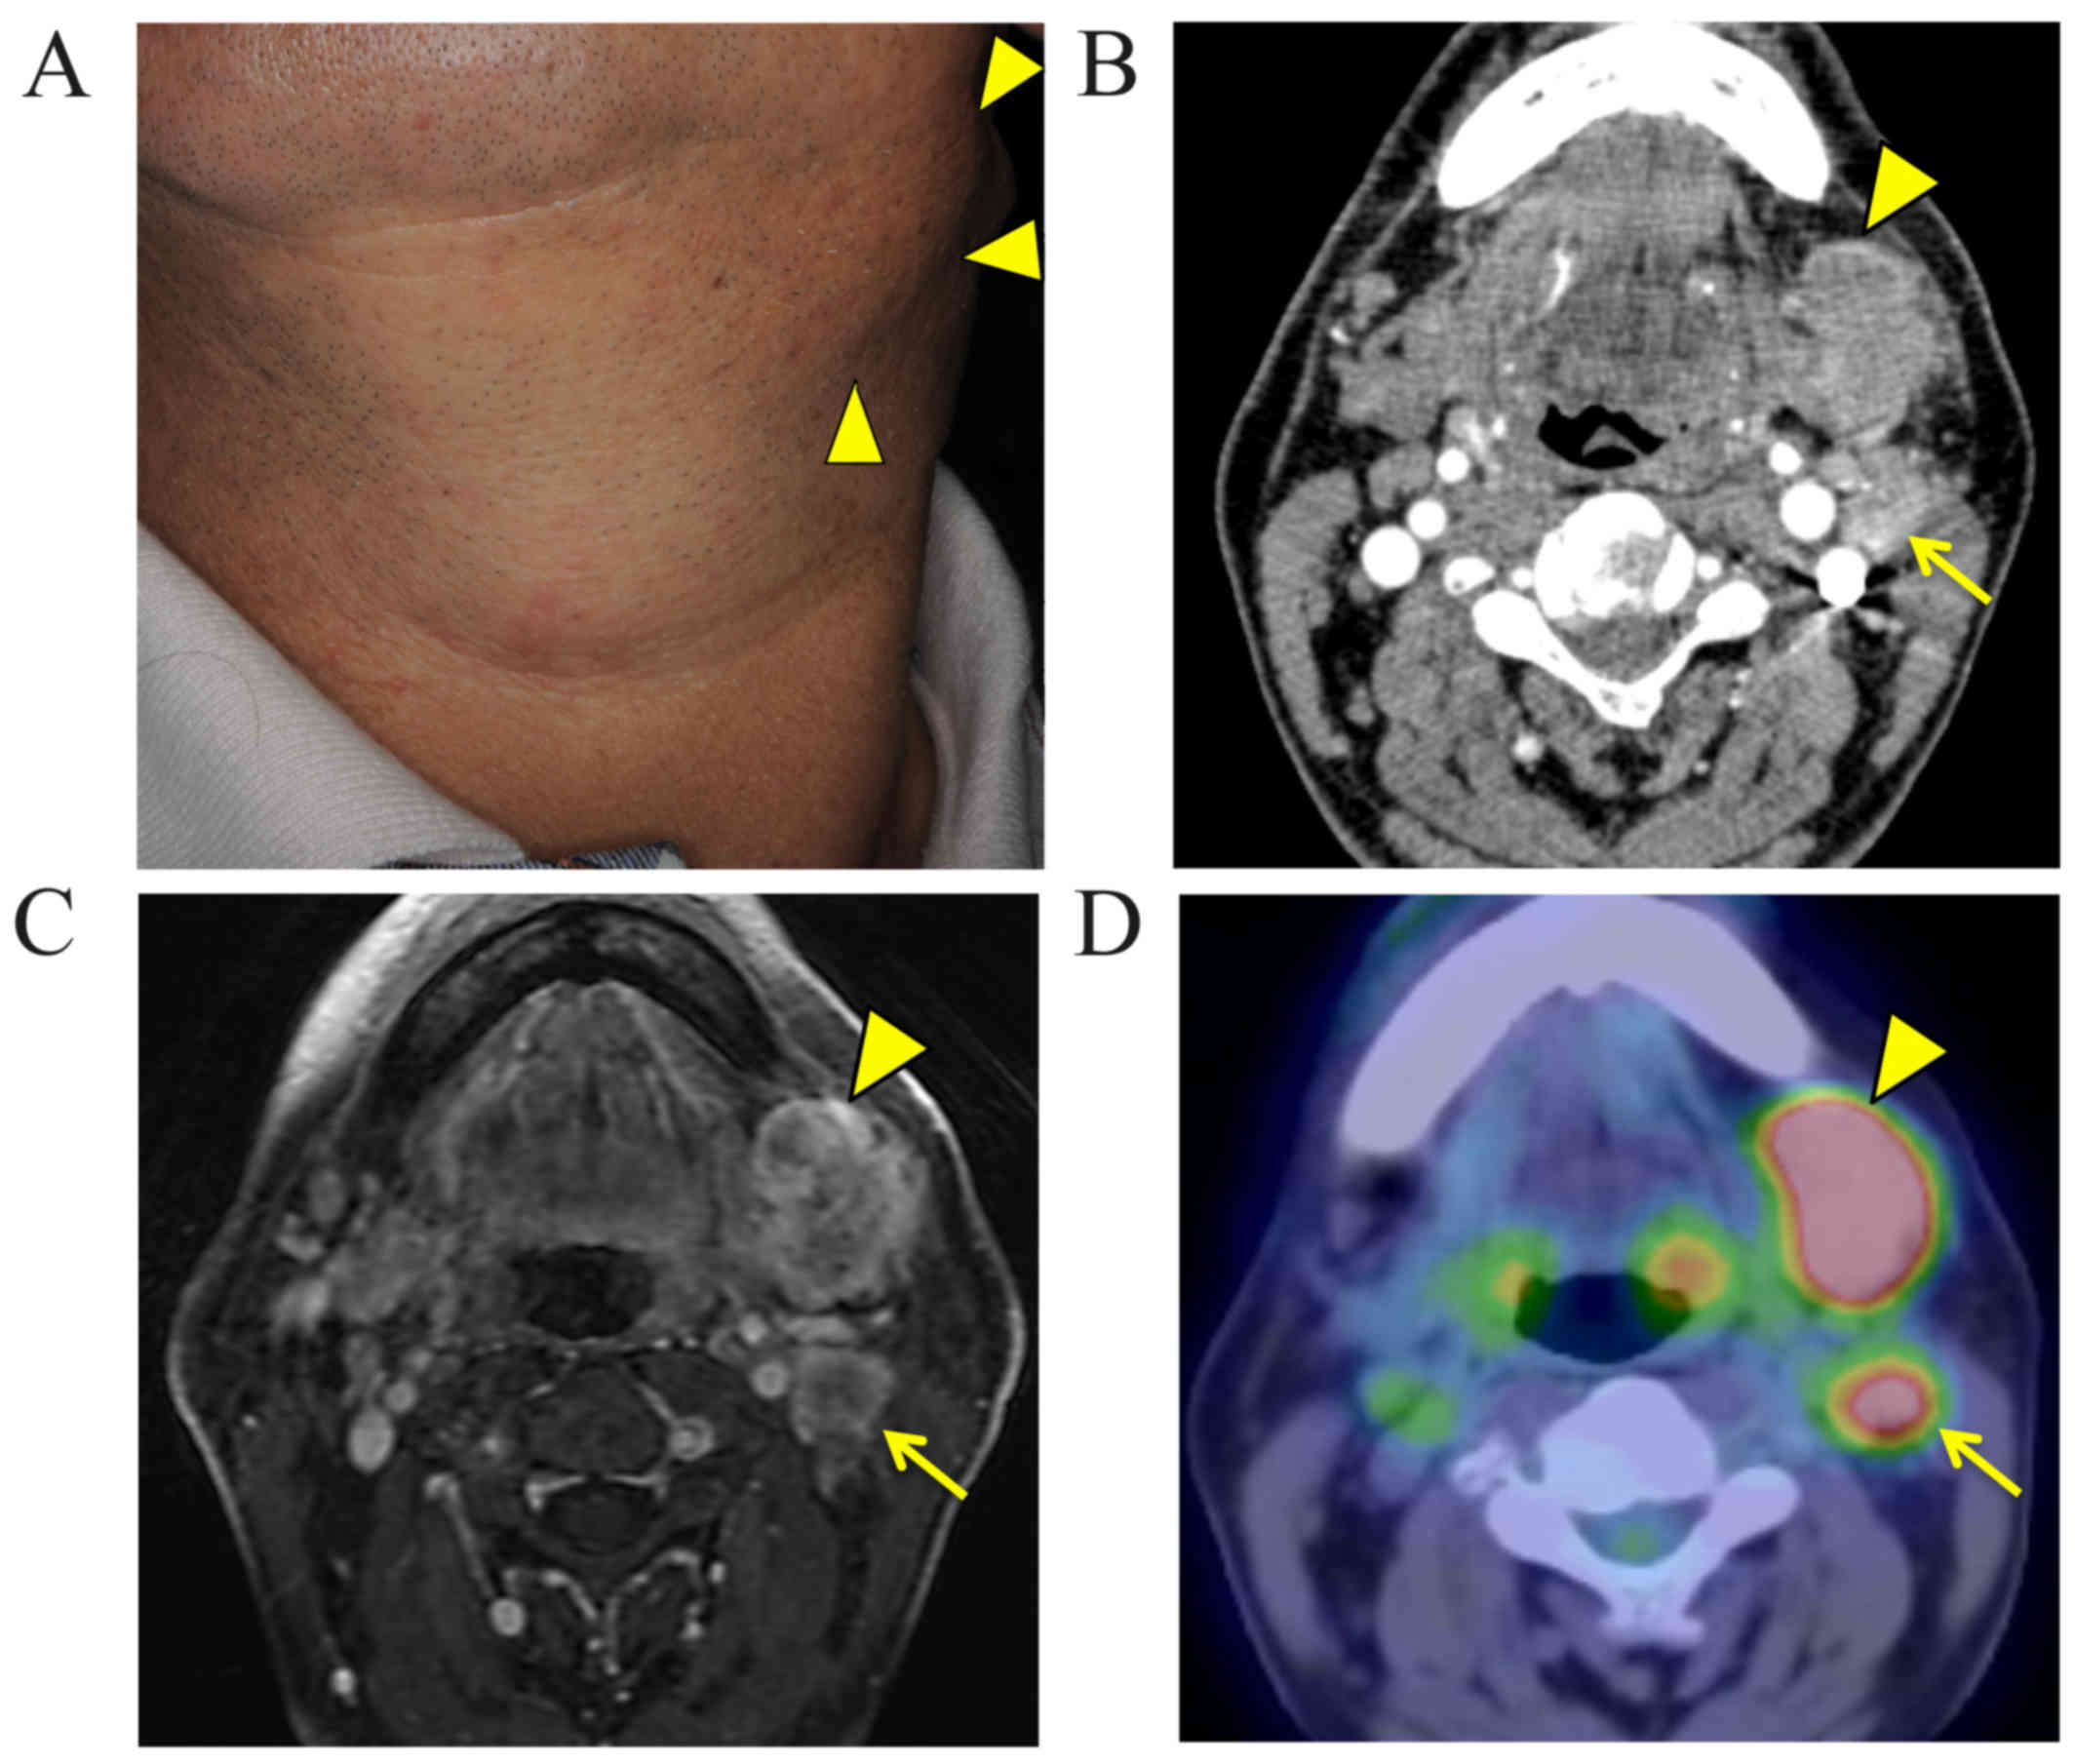

Salivary duct carcinoma is a highly aggressive disease with a poor prognosis. Surgical resection is currently the only curative treatment, as there is no effective systemic therapy for this malignancy. Recently, trastuzumab has been shown to exhibit therapeutic efficacy in the treatment of salivary duct carcinoma; similarly, molecularly targeted agents, such as cetuximab, are expected to be useful for salivary duct carcinoma treatment. We herein describe the case of a 56-year-old man diagnosed with salivary duct carcinoma in the left submandibular region, with ipsilateral multiple metastases to the neck lymph nodes. Radical resection of the tumor and submandibular gland with neck dissection were performed. One month after radical surgery, computed tomography (CT) scans indicated metastasis in the lower lobe of the left lung. CT‑guided transthoracic fine‑needle aspiration biopsy revealed a single metastasis and lung metastasectomy was immediately performed. The tumor cells of the primary lesion and those of the lung metastasis were immunohistochemically positive for epidermal growth factor receptor. One month later, multiple right lung metastases appeared, and the patient was treated with cisplatin/5‑fluorouracil (5‑FU) chemotherapy plus cetuximab, achieving a complete radiographic response. However, multiple lung metastases developed during adjuvant weekly cetuximab monotherapy. Subsequently, treatment with S‑1 and weekly cetuximab was initiated, and the multiple lung metastases have been maintained as stable disease for 5 months. To the best of our knowledge, this is the first report of cetuximab use for the treatment of salivary duct carcinoma. Although cisplatin/5‑FU chemotherapy plus cetuximab was efficacious in treating the lung metastasis, cetuximab monotherapy was insufficient for controlling tumor growth.